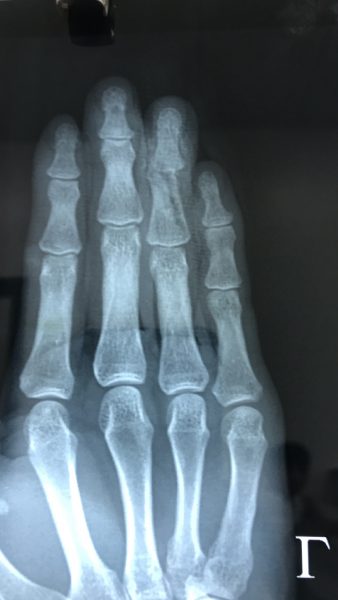

Hình ảnh chụp Xquang của bệnh nhân Chu Minh.P thấy rõ xương ngón tay số 4 đứt gẫy